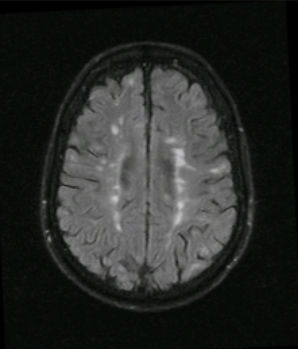

Multiple ring enhancing lesions should raise supsicion for….

Toxoplasma encephalitis

cns tuberculoma